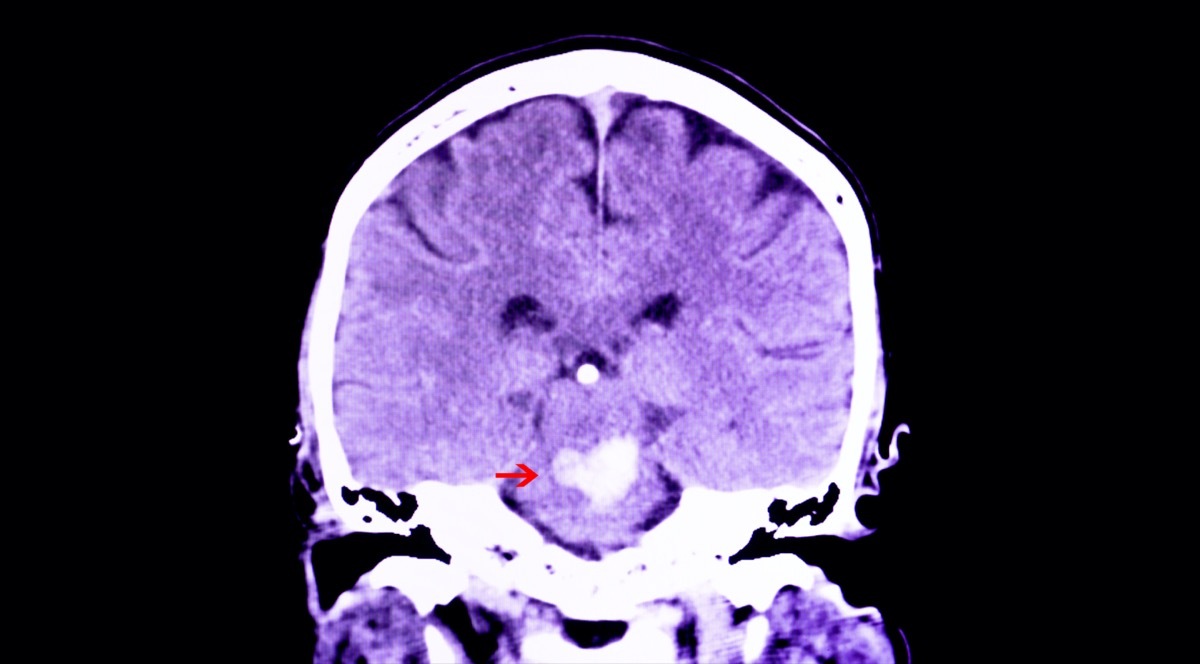

Sie können neurologische Erkrankungen haben

"Ein weiterer wichtiger Fund der Patienten, die an der post-akuten COVID-Klinik in Frankreich teilnehmen, war, dass nach ihrer akuten Covid-19-Erkrankung mehr als 1/4 neue neurologische Anzeichen und Symptome entwickelte", sagt Dr. Hernandez-Romieu. "Dazu gehörten aber nicht auf kognitive Dysfunktion, ausgewogene Störungen, Parästhesie und Schluck- und Sprachstörungen."

"SARS-COV-2-Infektion kann auch zu spezifischen Komplikationen wie Schlaganfall, Guillain-Barre-Syndrom und einer Entzündungsstörung von Multisystem führen, die längere Symptome und Behinderung verursachen können", sagt Dr. Hernandez-Romieu.